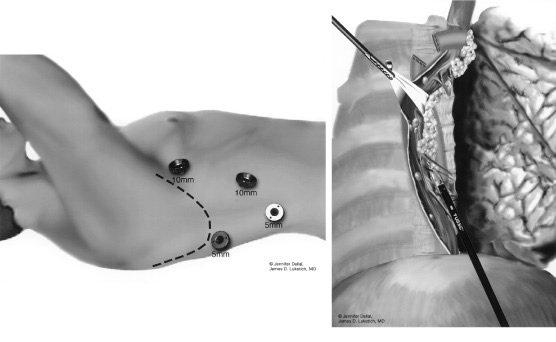

Esofagectomia com interposição de segmento antiperistáltico do cólon. A, Incisões usadas para realizar a esofagectomia, esofagostomia cervical, piloromiotomia e gastrostomia. B, Extensão da ressecção esofágica (área sombreada). C, Preparo do segmento de cólon esquerdo (área sombreada) para interposição baseada na artéria cólica média (perceba os locais de interrupção da vascularização, que preservam a integridade da arcada vascular). D, Operação completa.